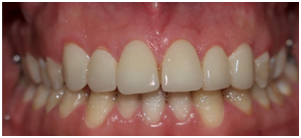

Static and dynamic occlusion was scrutinized. Minor adjustments were realized by means of fine diamond bur. Finally, the margins of the bonded veneers were finished and polished. The patient was satisfied with both esthetic and functional outcome (Figure 11) (Figure 12).

Figure 12 Final result: a: intra oral view, b: lateral view, c smile.